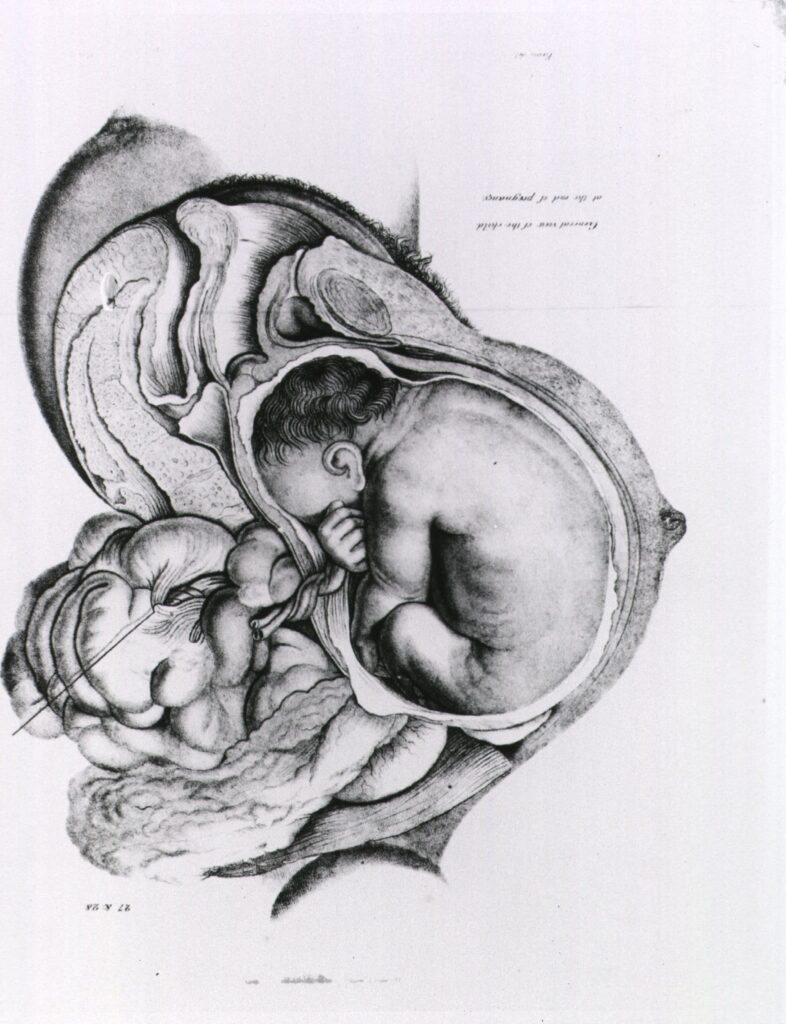

Варто завжди памʼятати, що саме Бог, а не люди — це творець життя. Для Бога люди — це найбільша цінність, якими б маленькими вони не були. Зачаття і вагітність — це неймовірно дивовижний і таємничий процес. Ось з яким захопленням описує це псалмоспівець:

Ти створив нутрощі мої,

Псалом 138:13-16

зіткав мене в утробі моєї матері.

Буду славити Тебе за те,

що дивовижно й чудово

створений я.

Дивні діяння Твої,

і душа моя добре це знає!

Не були приховані

від Тебе мої кості,

коли я був створений у таємниці,

витканий у глибинах землі.

Твої очі бачили мій зародок,

і в книзі Твоїй були записані всі дні,

призначені для мене,

коли жодного з них ще не було.